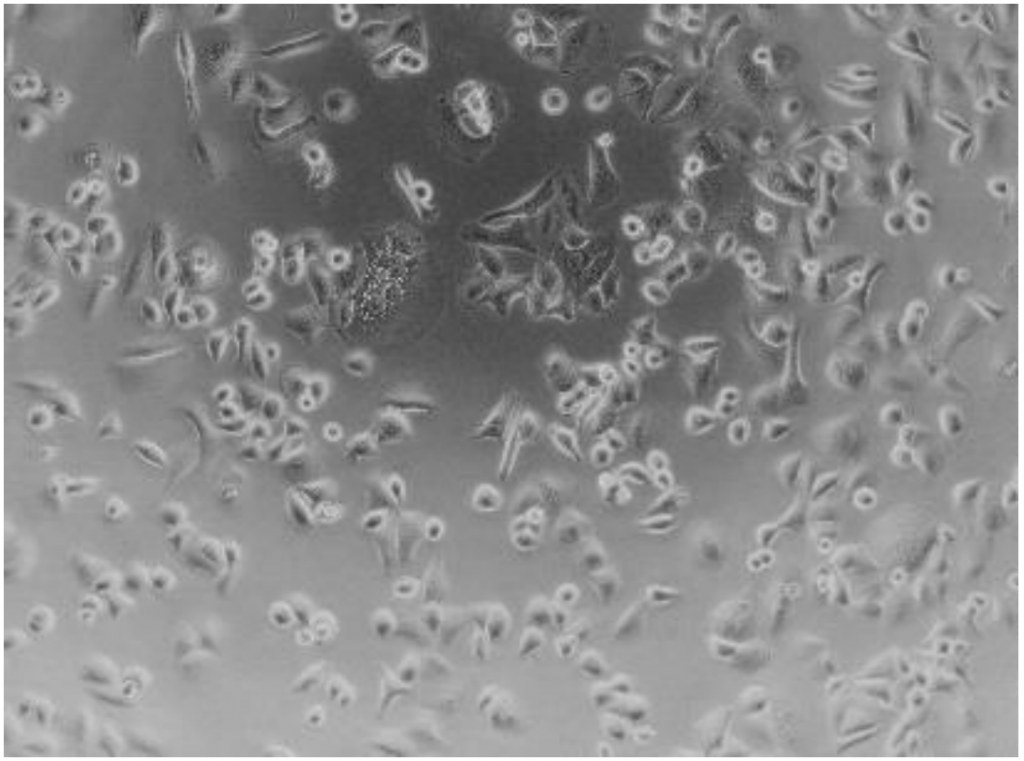

Une viabilité cellulaire de plus de 80% est attendue après décongélation, les cellules conservant une morphologie saine. |